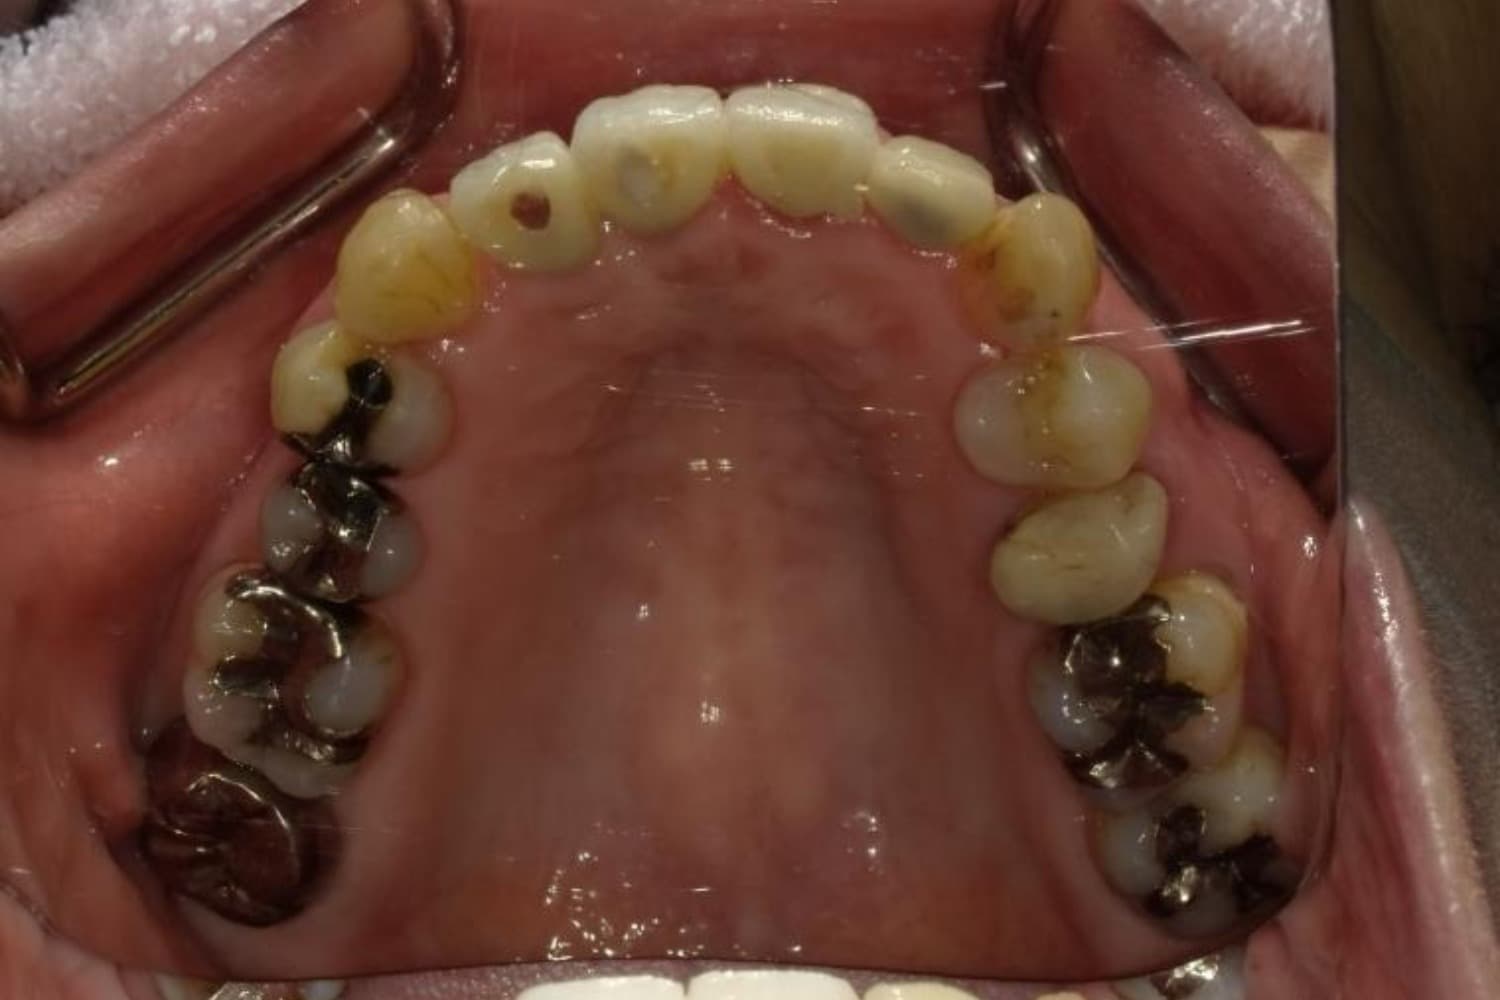

下顎大臼歯3本欠損症例

Before

After

左下第一大臼歯は保存が困難な状態であったため抜歯をおこないました。あわせて、ご来院時から欠損していた右下第一・第二大臼歯も含め、欠損部の補綴方法についてご説明し、インプラント治療を選択されました。

年齢

60歳

性別

男性

主訴

左下の第一大臼歯は別の医院で治療中でしたが、治療が思うように進まず、加えて他の箇所にも痛みが続いたことから、当院にご相談いただきました。

治療期間

10ヵ月

費用

140万円

副作用・リスク

インプラント治療は外科的な処置を伴い、多少の腫れや痛みが出ることがあります。 多くの場合は鎮痛薬で和らげることができます。